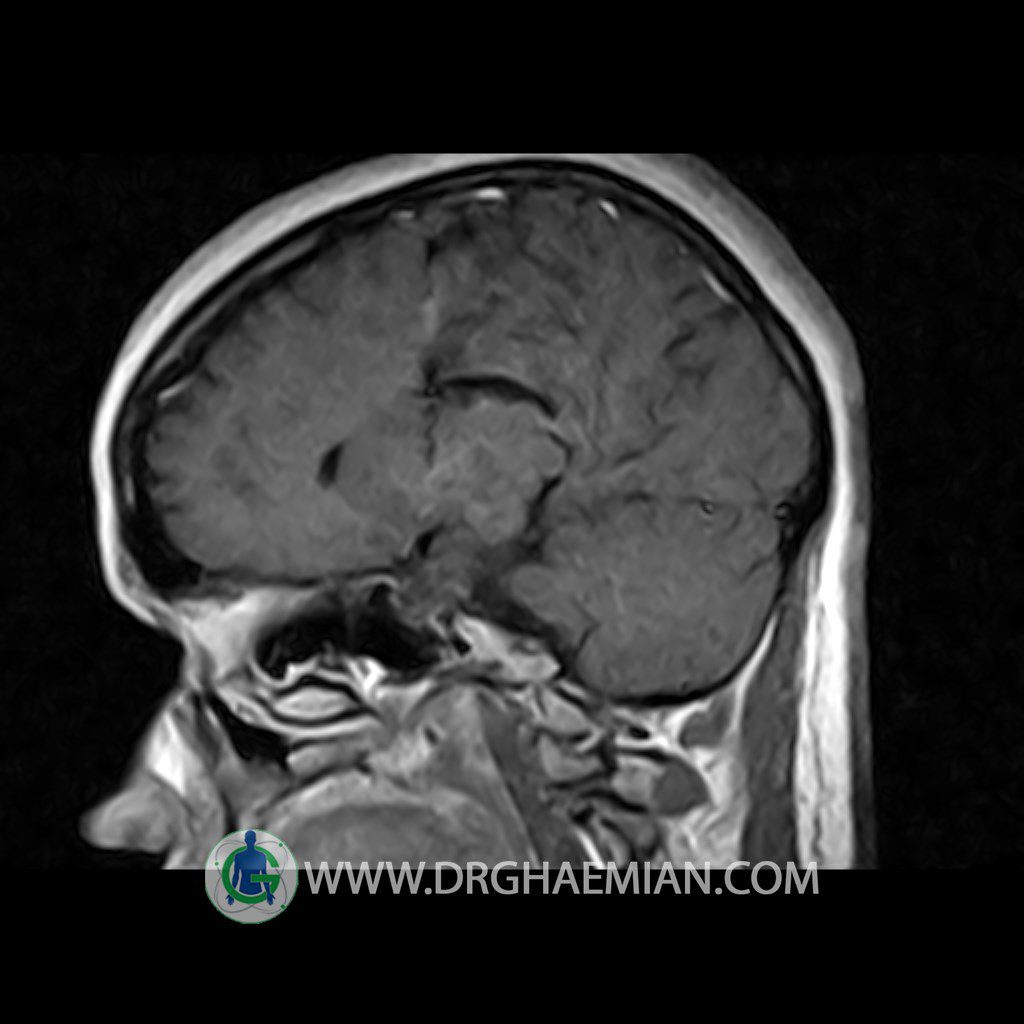

ام آر آی هیپوفیز یک روش تصویر برداری است که از غده هیپوفیز (غده ایی کوچک در مغز که هرومون ها و دیگر غدد بدن را کنترل می کند) و ناحیه های پیرامونش در مغز تصاویری ایجاد می کند. در این کیس سلای نسبتا خالی در ناحیه هیپوفیز بیمار مشاهده می شود.

Technique: Axial , coronal T1 , Axial , coronal , sagittal T2 , Axial, coronal T1 post Gd & 64 dynamic thin coronal slices.

– Extension of suprasella cistern to sella with thin pituitary gland in floor of sella ( partial empty sella )

is seen